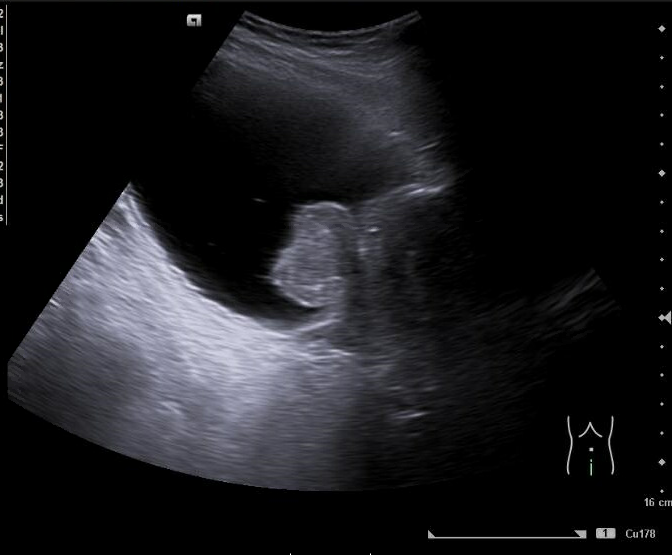

Imagen 1. Riñón derecho: hidronefrosis grado II. Tamaño 11.2 cm.